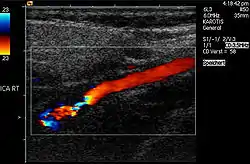

تَصَلُّبِ شَرایین یا سختاک سرخرگها آترواسکلروزیس (atherosclerosis)، نام یک بیماری در رگها و نوعی آرتریواسکلروزیس است که با رسوب لیپید و کلسترول کمچگال بر روی دیواره داخلی سرخرگهای با قطر متوسط و بزرگ، مشخص میگردد. نتیجه این فرایند تشکیل پلاکهای فیبری-چربی (آتروما) بوده که با افزایش سن رفته رفته ازدیاد مییابد و موجب تنگی رگ (استنوزیس) یا دیگر عواقب میگردد.[1]

| روند شکلگیری آترواسکلروزیس (تصلب شرایین) در طی سالیان، درون یک رگ. | |